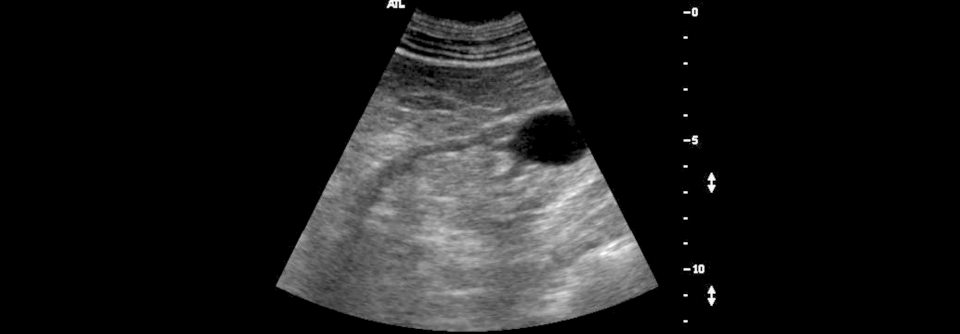

Bei CKD zeigt sich im Ultraschall oft eine diffuse Atrophie der Nierenrinde mit echogenem Parenchym. Bei CKD zeigt sich im Ultraschall oft eine diffuse Atrophie der Nierenrinde mit echogenem Parenchym. © Science Photo Library / Steven Needell

Die Neuerungen in der aktualisierten S3-Leitlinie zur chronisch eingeschränkten Nierenfunktion beginnen mit der Terminologie. Zur besseren Verständlichkeit übernehmen die DEGAM und weitere beteiligte Fachgesellschaften nun die Begrifflichkeiten der DGfN* (siehe Kasten). Diagnostisch plädiert das Autorenteam bereits beim Verdacht auf eine chronische Nierenkrankheit (CKD) für eine Sonografie des Urogenitalsystems.